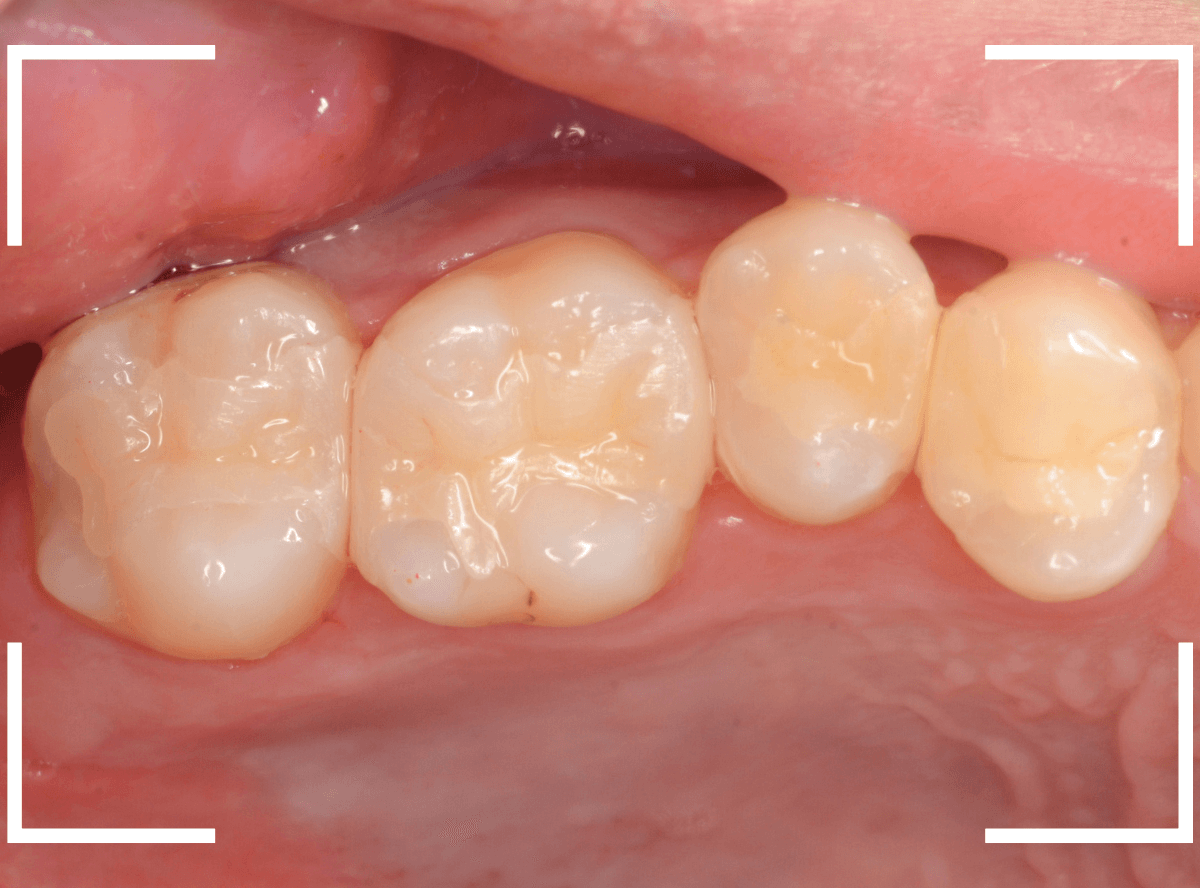

最終setした状態です。

左側の大臼歯2本が、ジルコニア・インレー

右側の小臼歯2本が、E-MAX・インレー

になります。

見た目にほとんど遜色ない仕上がりにできました。

普段あまりしない、4歯連続のインレー治療でしたが、精密に仕上げ・setする事が出来てホッとしました。